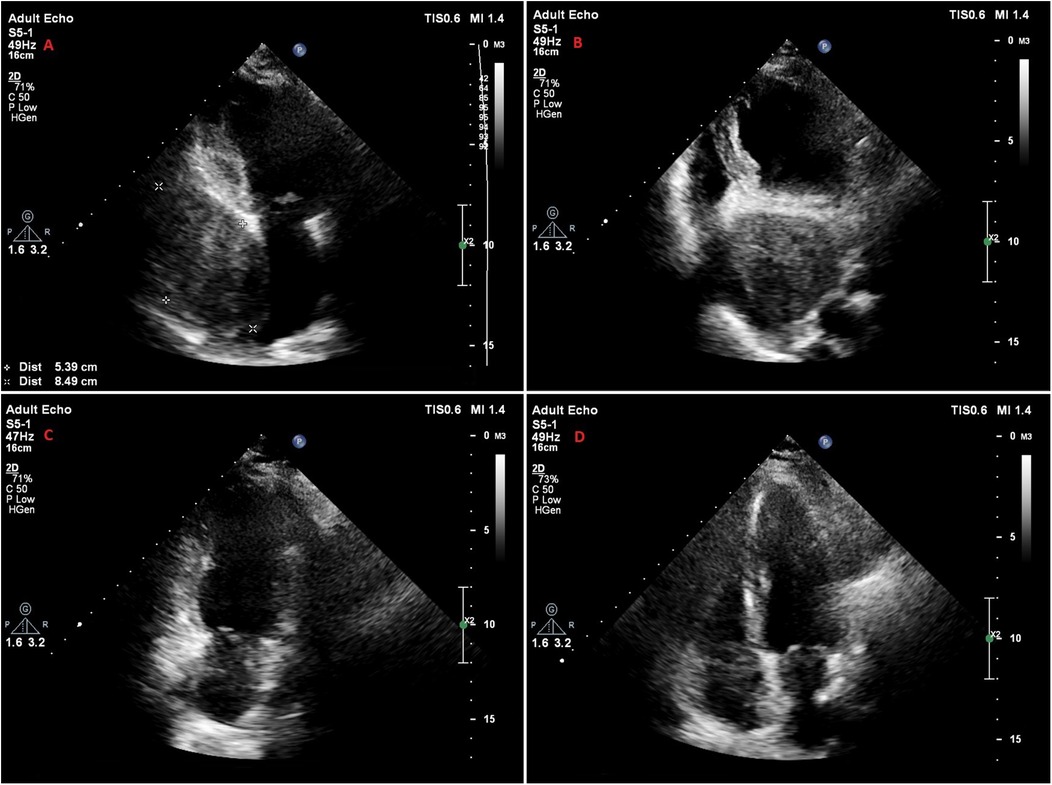

A 47-year-old female patient applied to the cardiology outpatient clinic with complaints of exertional dyspnea and intermittent chest pain. The patient's New York Heart Association (NYHA) functional capacity score was 2–3. Chest pain was unrelated to exertion. The patient had hypertension and was normotensive under perindopril 10 mg and amlodipine 10 mg treatments. She was a nonsmoker and had Class I obesity with a body mass index of 30.8 kg/m2. Physical examination was normal. Laboratory parameters showed an elevation of low-density lipoprotein at 187 mg/dl and an elevation of N-terminus pro-B-type natriuretic peptide (NT-proBNP) at 684 pg/ml. The electrocardiogram showed sinus rhythm with a rate of 83 bpm and no abnormalities. Transthoracic echocardiography (TTE) revealed a well-circumscribed hypoechoic mass lesion measuring 8.5 cm × 5.4 cm, located behind the posterior walls of the left atrium and left ventricle, causing significant compression of the left atrium (Figures 1A,B). Other findings of TTE were; normal left ventricular systolic function with a left ventricular ejection fraction (LVEF) of 65%, mild dilatation of the left atrium with a left atrial volume index (LAVI) of 36 ml/m2, mild mitral valve regurgitation, mild tricuspid valve regurgitation, tricuspid valve regurgitation velocity 3.2 m/s, grade II diastolic dysfunction and normal right ventricular systolic function with a tricuspid annular plane systolic excursion of 22 mm. Transesophageal echocardiography (TEE) was performed for detailed evaluation of the mass and its neighbors. TEE showed a mass containing a cystic lesion that caused significant compression of the left atrium (LA) and mild compression of the inferior vena cava (IVC) (Figure 2). No pulmonary venous return anomaly or obvious compression of the pulmonary veins was detected on TEE. Thoracic computed tomography (CT) angiography revealed a pericardial mass lesion measuring 10.1 cm × 8.1 cm × 5.2 cm in size, with regular borders and soft tissue density, located in the posterior mediastinum, adjacent to the LA and descending aorta, creating significant compression on the esophagus (Figure 3). The whole-body 18F-fluorodeoxyglucose (18F-FDG) positron emission tomography (PET)-CT images revealed a giant pericardial mass with mild to moderate 18F-FDG avidity (Figure 4). No metastatic lesions were detected. Magnetic resonance imaging (MRI) showed a well circumscribed, T1-hypointense and T2-hyperintense pericardial mass. The mass was observed to have homogeneous signal intensity on T1 and T2-weighted images. There was no direct myocardial infiltration and/or left atrial invasion (Figure 3). Contrast-enhanced images were not obtained for the patient who had a history of anaphylactic shock due to a gadolinium-based contrast agent. CT and MRI showed that the mass did not cause myocardial involvement, however, the mass could not be demarcated from the LA and IVC. The coronary angiogram did not detect obstructive coronary artery disease or coronary artery compression due to the mass. For the histological diagnosis of this giant pericardial mass, EUS-FNA was performed. Histological evaluation revealed foci of spindle cell proliferation forming Antoni A and Antoni B areas. Immunohistochemical studies revealed that these spindle cells stained diffusely positive for S100, which was consistent with schwannoma. The Ki-67 index was less than 1%.

Figure 2

Figure 2. Transesophageal echocardiography images of the patient. (A) Midesophageal 4-chamber view. (B) Biplane view showing that the mass contains an area of cystic degeneration. (C) Midesophageal long axis view showing that the mass is compressing the left atrium, mitral annulus and partially the left ventricle. (D) Midesophageal bicaval view showing the mass creating mild compression on the inferior vena cava.